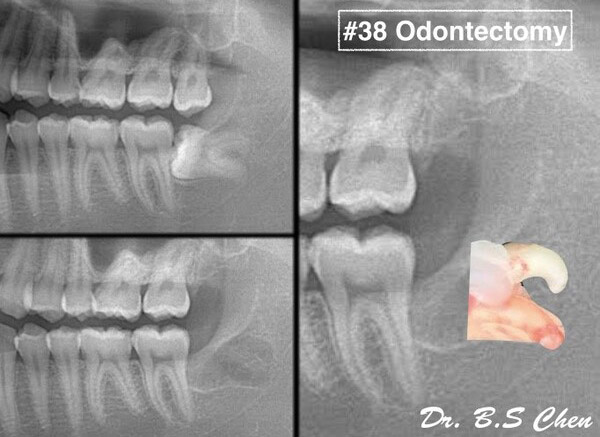

微創智齒手術案例分享